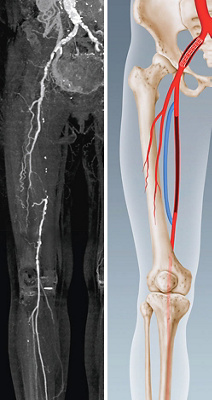

Abb. 1 (links)

Magnetresonanzuntersuchung der Gefässe (Angio-MRI)

Abb. 2 (rechts)

Schematische Darstellung des Bypasses und des Beckenstents

So wird Herr W. einer angiologischen Untersuchung unterzogen. Dabei kommt zum Vorschein, dass neben einer hochgradigen Verengung in der rechten Beckenarterie auch ein langstreckiger Verschluss der Oberschenkelarterie rechts besteht. Im Rahmen einer interdisziplinären Besprechung wird das bestmögliche therapeutische Vorgehen erörtert. Die Verengung der Beckenschlagader (Arteria iliaca) eignet sich gut für eine kathetertechnische Behandlung. Dabei wird sie zuerst mittels eines Ballons aufgedehnt und anschliessend mit einem Stent als Gefässstütze offengehalten. Gleichzeitig wird der Gefässverschluss am Oberschenkel mit einem Venen-Bypass von der Leiste bis zum Knie in einer offenen Operation behandelt. Das heisst, die verengte Arterie wird mit Hilfe eines Venenstücks überbrückt. In diesem Fall ist es die oberflächliche Vene des gleichen Beins, die mikrochirurgisch präpariert und als Bypass verwendet wird. Am Bein ist ein Bypass mittels körpereigener Vene einem Kunststoff-Bypass stets vorzuziehen, weil ein Venen-Bypass statistisch gesehen eine viel längere Offenheitsrate als ein Kunststoff-Bypass aufweist.